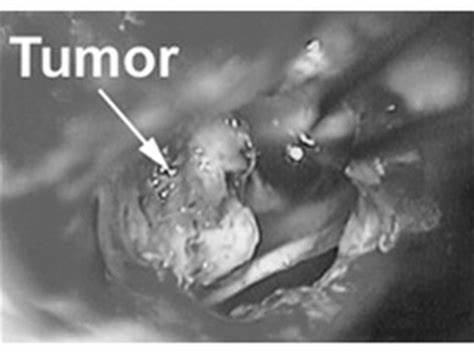

听神经瘤也被称为前庭神经鞘瘤,是一种生长缓慢的肿瘤,通常不需要任何治疗,但有时它可能快速增长,这个时候治疗是必要的。外科手术是听神经瘤常见的治疗方式,也是一种成功的治疗方式。听神经瘤手术风险大吗?

不同的外科医生设计了不同的方法来达到内听神经道和桥小脑角。每种方法都有各自的优缺点。通常有三种手术入路,经迷路入路、颅中窝入路和乙状窦入路。

听神经瘤的手术治疗本身就是一种危险的治疗方法。不管用什么方法打开头骨并切除一部分,都不可能被认为是顺利的手术。无论何种原因,脑外科手术本身都会给病人的生命带来很大的风险。也顺利取决于个人需求像病人喜欢听力损失的副作用但希望的完整切除肿瘤通常会像经迷路的方法而病人倾向于听力和牺牲可以接受肿瘤更可能会与颅中窝方法由于其高储蓄听力能力的机会。但要从三种方法中选择一种进行风险因素分析,现有方法是更佳选择。它是三种手术中较顺利的,但有明显的术后效应,如完全失聪、耳鸣等。那么如何降低听神经瘤手术风险?